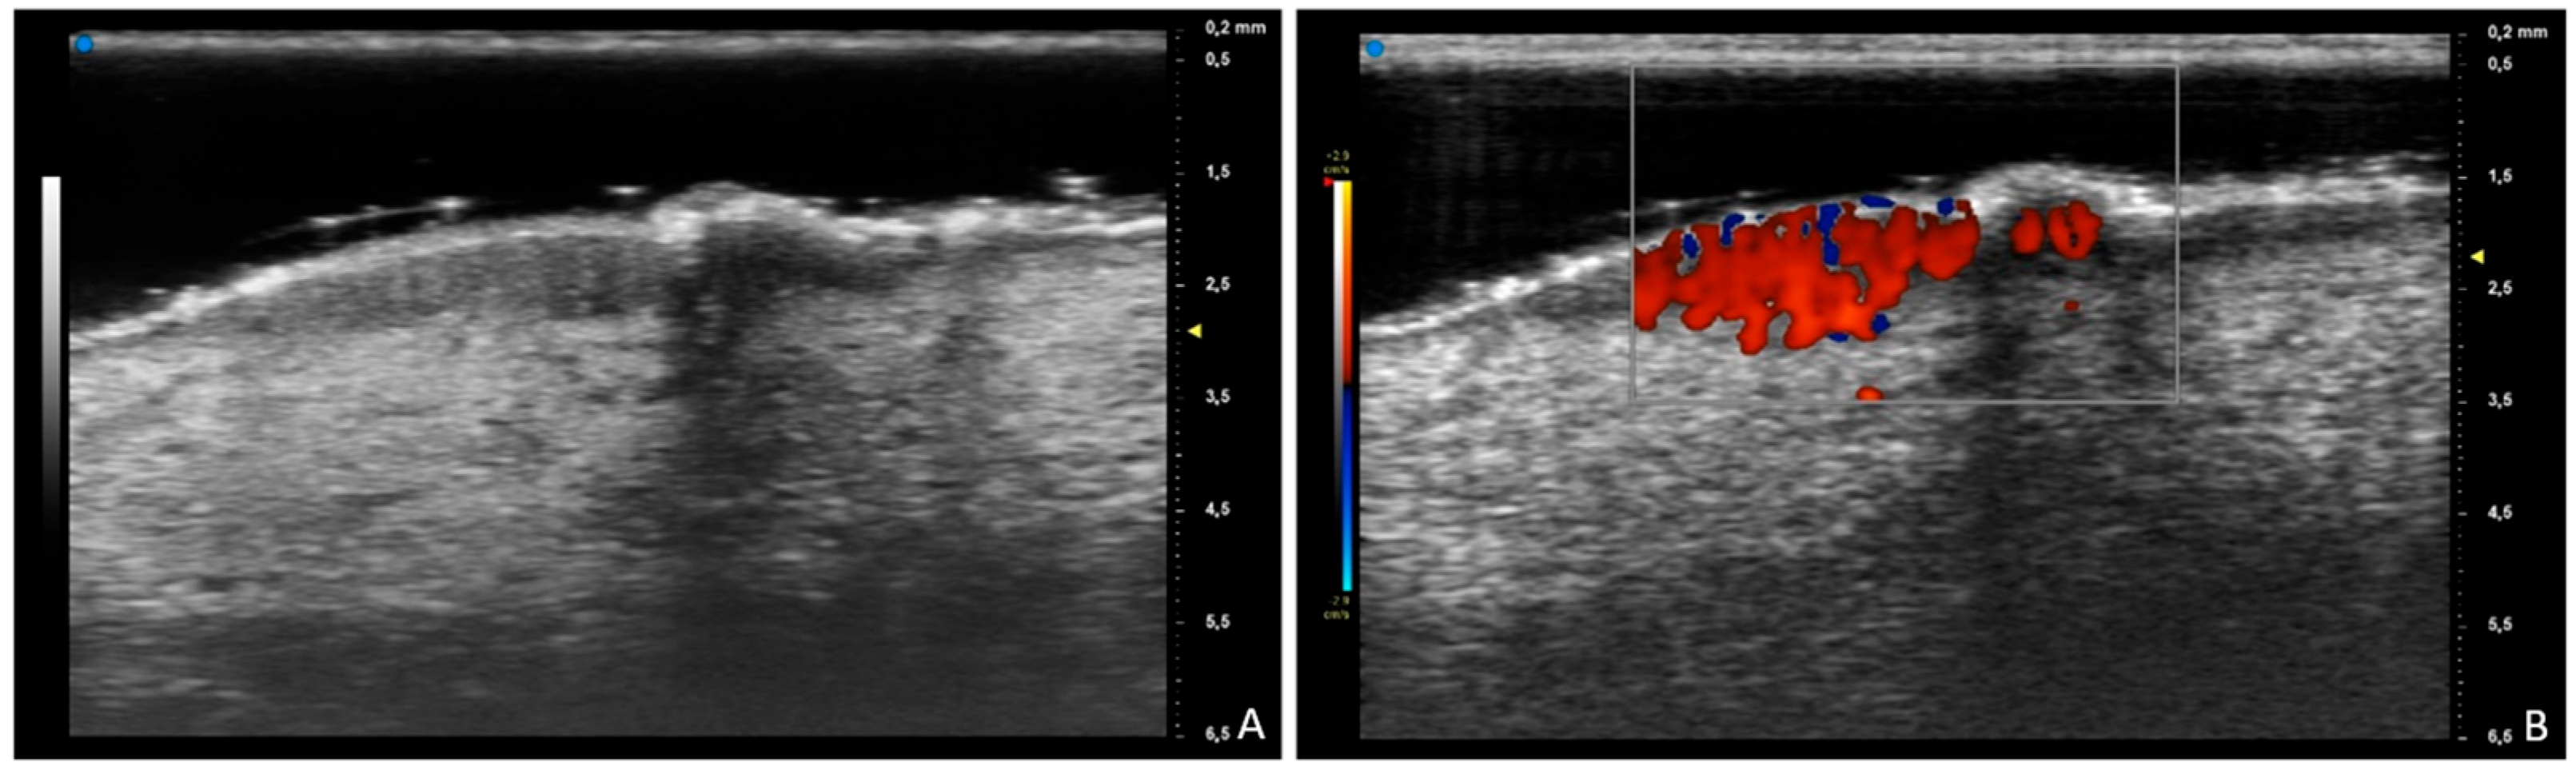

Prurigo Nodularis at Ultra-High-Frequency Ultrasound

Michelucci, A.; Tagliati, C.; Manzo Margiotta, F.; Salvia, G.; Fogante, M.; Rizzetto, G.; Corvino, A.; Molinelli, E.; Offidani, A.; Simonetti, O.; et al. Prurigo Nodularis at Ultra-High-Frequency Ultrasound. Diagnostics 2025, 15, 1624. https://doi.org/10.3390/diagnostics15131624